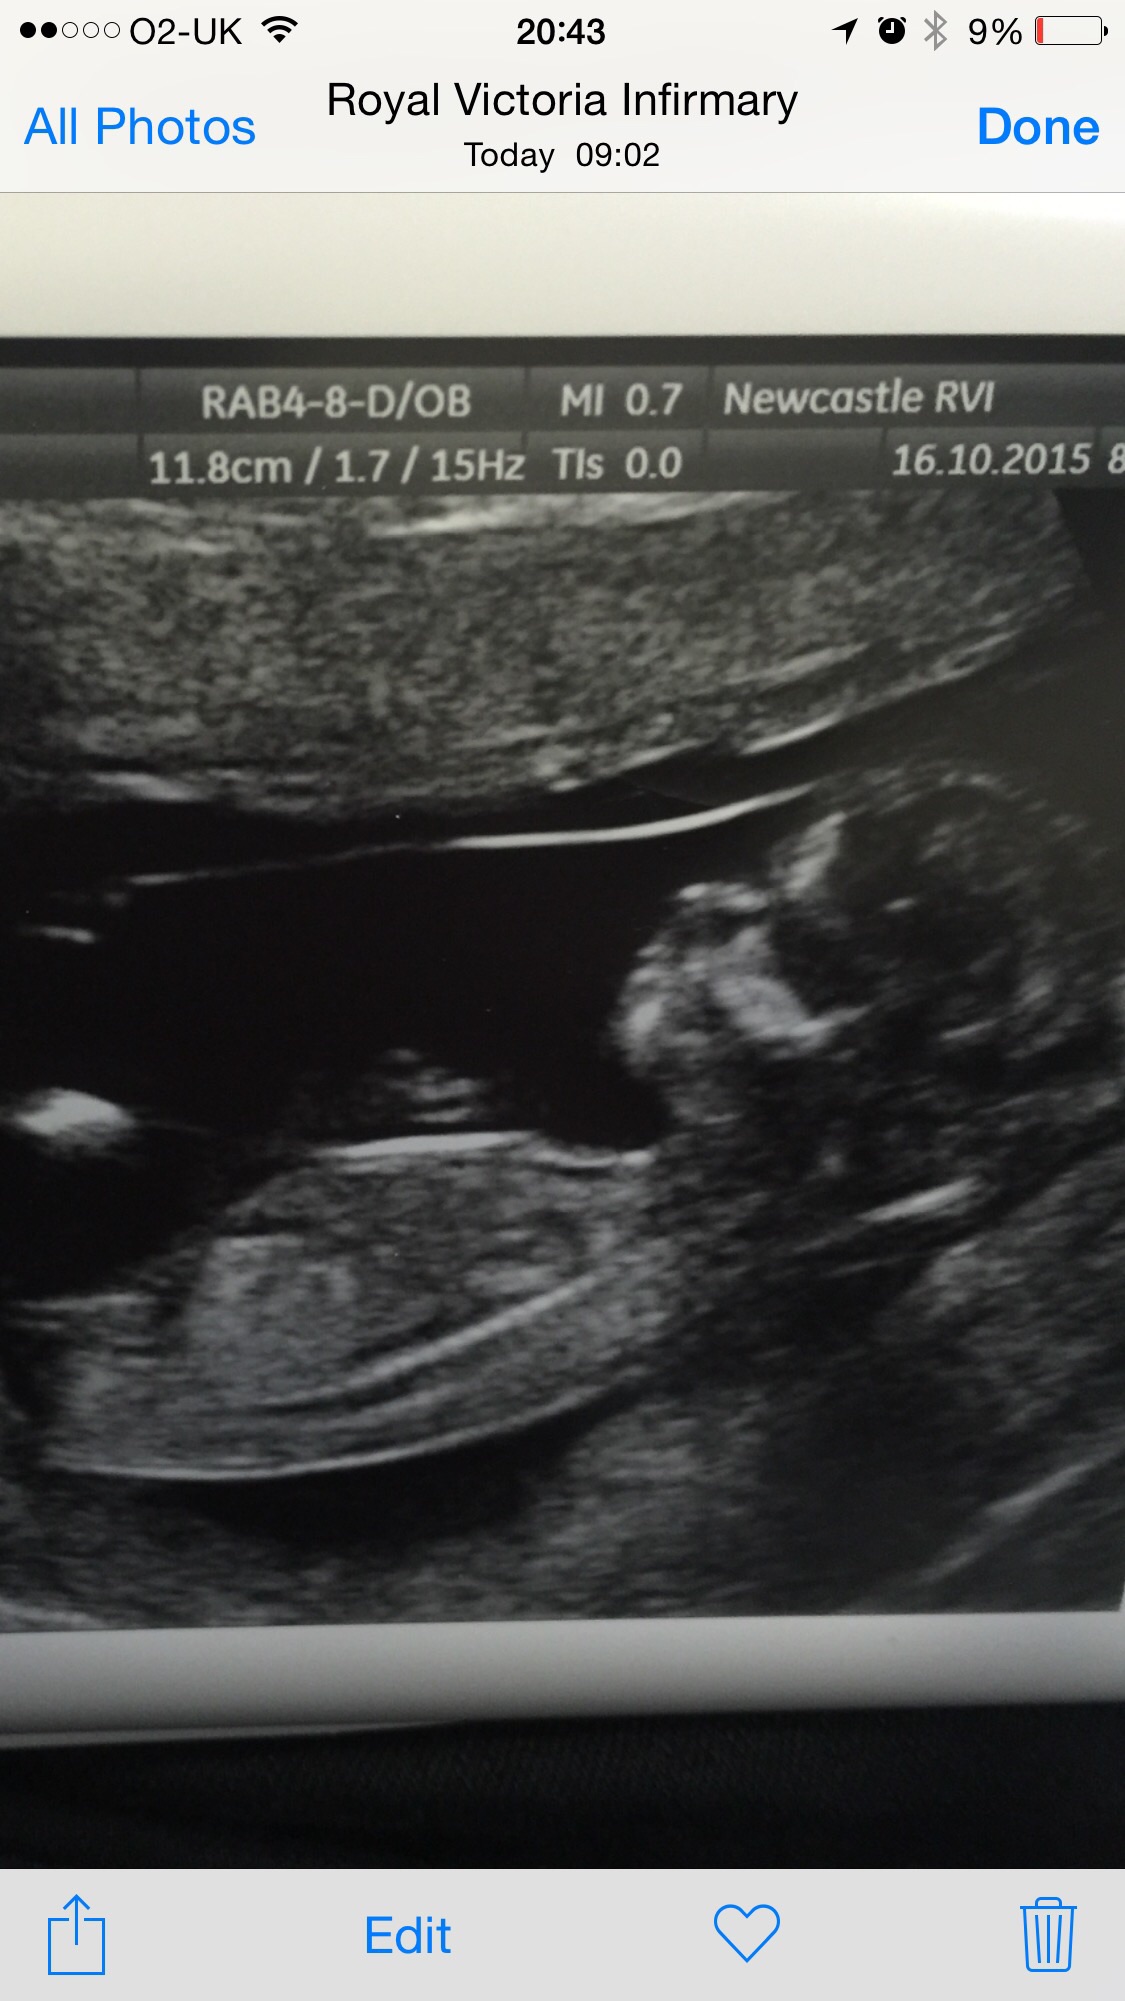

Any guesses on the gender of this 12week 6day ultrasound

Any guesses on this 12wk 6day ultrasound pic?